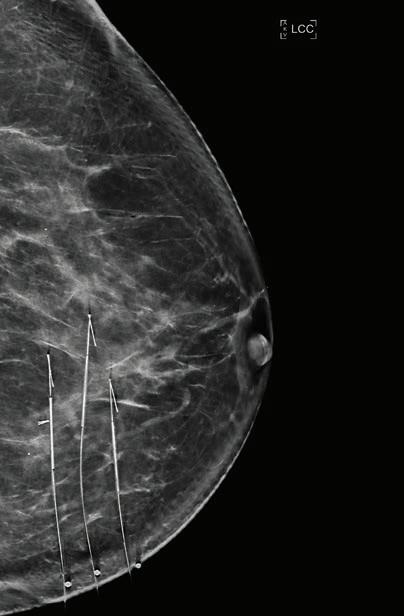

PARTNERS 29 Antimicrobial stewardship Dr Ramya Raman 30 Managing osteoarthritis without surgery Dr Daniel Heredia 42 Advances in resection of impalpable breast lesions Dr Wen-Chan Yeow 45 Transcatheter mitral valve repair Dr Kevin Chung 49 What’s next for TMS? A/Prof Jennifer Rodger & Dr Jaroslaw Hryniewicki